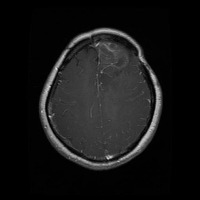

This project has created a labeled MRI brain tumor dataset for the detection of three tumor types: pituitary, meningioma, and glioma. The dataset contains 2443 total images, which have been split into training, validation, and test sets. The training set has 1695 images, the validation set has 502 images, and the test set has 246 images.

- Image types: MRI scans

- Pituitary tumor

- Meningioma tumor

- Glioma tumor

- No Tumor

- The images have been labeled by medical experts using a standardized labeling protocol.

- The labels include the type of tumor and the location of the tumor.